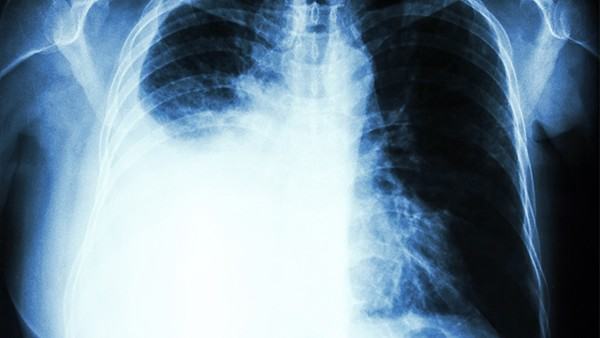

首先,我们需要了解气胸的分类。气胸可以分为原发性和继发性两种。原发性气胸多为年轻男性出现,与患者个体发育异常有关,通常不需要手术干预,绝大多数患者经过适当休息和观察会自行康复。继发性气胸则是由其他疾病,如肺部疾病或外伤引起的,需要根据具体情况进行治疗。所以,在回答气胸患者是否适合运动的问题时,应根据具体情况进行综合分析和判断。